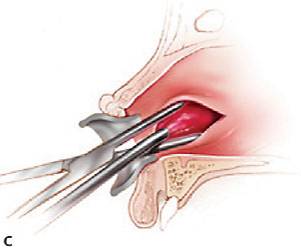

| Incision & Drainage | |

1) Contact bone at a 45 degree angle |

2) Insert hemostat CLOSED, dissect open, remove opened |

3) Insert drain w/ tissue pick-ups/hemostat (You can place a suture thru the drain prior to placement) |

4) Place 1-2 silk sutures to secure the drain |